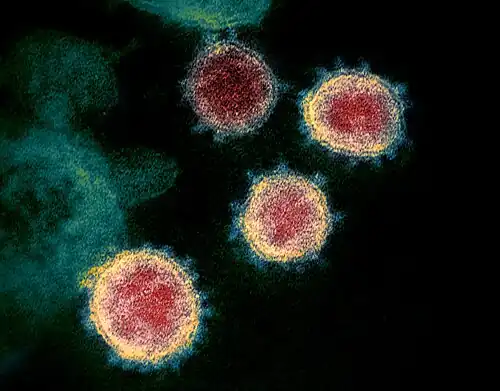

- COVID-19 pandemic: Chinese authorities first publicly confirm that there is human-to-human transmission of severe acute respiratory syndrome coronavirus 2.[57]

- 31 January – Scientists and journalists report overviews of the novel coronavirus SARS-CoV-2 outbreak, later classified as a pandemic, including on the infectability, mortality rate, incubation time, worldwide ability to contain the outbreak, and estimated time for a vaccine (along with a comparison with other similar outbreaks).[68][69][70]

−0.18-day pulse cycle.[90][91][92][93][94] - 4 February – The drugs remdesivir and chloroquine are shown to effectively inhibit SARS-CoV-2 in vitro.[95][96]

- Scientists report that bats' heightened immune responses to their viruses, of which SARS-CoV-2 is a likely example, can facilitate the evolution of rapidly-replicating viruses that likely cause enhanced virulence following emergence into secondary hosts with other immune systems such as humans. The researchers used a combination of in vitro experimentation and within-host modeling to explore the impact of the previously already well-known unique bat immunity on virus dynamics.[115][116]

- Scientists present an atomic-level image using cryogenic electron microscopy of an essential protein used to access cells by the SARS-CoV-2 novel coronavirus that is responsible for the coronavirus disease 2019 (COVID-19) and COVID-19 pandemic. This image may help in more quickly finding a cure or to develop medical countermeasures (MCMs) for the viral infection.[149][150]

- 20 February – Scientists use the world's most powerful supercomputer, SUMMIT, to screen molecules which bind to either SARS-CoV-2's spike protein or to its human ACE2 interface and publish their results, including a ranked list of compounds which may be repurposed to attenuate COVID-19, in a preprint.[154][155]

- Initial phase 1 testing of a Coronavirus vaccine from biotechnology company Moderna is reported to start soon.[173][174]

- Scientists report that they have identified a second enzyme in the cell membrane of lung cells essential for entry of SARS-CoV-2 into the cells after the enzyme ACE2 has been identified earlier by other researchers. They found that the protease TMPRSS2 is split by the virus' spike protein to enter the cell and that the TMPRSS2-inhibitors Camostat and, in a second report by other researchers on 18 March, Nafamostat may be potential treatments as they reduced the probability of the virus entering cells in vitro.[211][212][213]

- Chinese news announces that the first confirmed case of the COVID-19 disease, caused by the SARS-CoV-2 virus, was traced back to a 55-year-old patient in Hubei province, and was reported in a Chinese newspaper on 17 November 2019.[248] To date (14 March 2020), 67,790 cases and 3,075 deaths due to the virus have been reported in Hubei province; a case fatality rate (CFR) of 4.54%.[248]

- 17 March – Scientists report that the novel SARS-CoV-2 virus, which causes the COVID-19 disease, and is responsible for the COVID-19 pandemic, originated naturally, and not otherwise,[268][269] although Chinese medical researchers, including Shi Zhengli, in Wuhan, China, were studying bat coronaviruses in ways that included modifying virus genomes to enter human cells, as early as 2014,[270][271] in testing laboratories that were determined to have significant safety issues by U.S. scientists in 2018.[272][273][274]